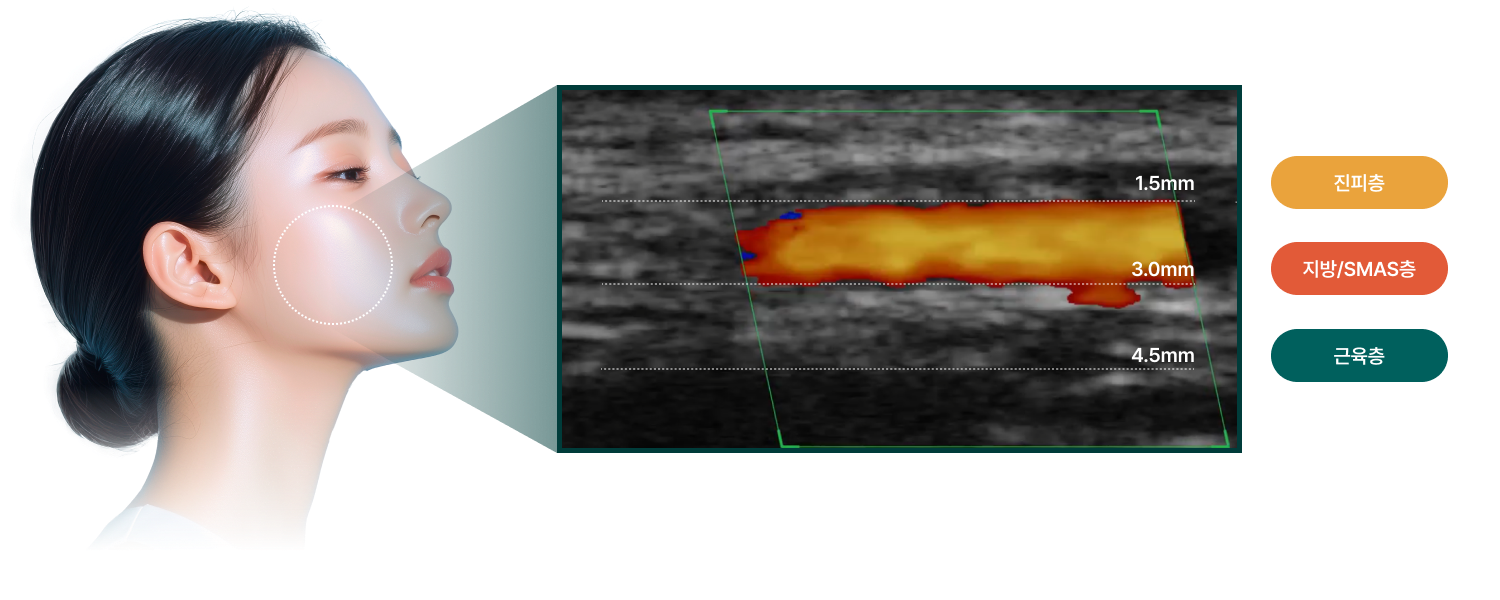

루브의 리프팅은 감(感)이 아닌 데이터로 설계됩니다.

피부층을 초음파로 정밀하게 진단하고,

당신의 얼굴 구조에 꼭 맞는 3단계 커스텀 플랜으로 정확한 타겟층에 에너지를 전달합니다.

초음파 디자인 (SONOMI 진단)

초음파 진단장비 SONOMI로 피부층을 실시간 확인하여 자극이 필요한 타겟층(SMAS, 진피 등)에만 정확한 에너지를 전달합니다.